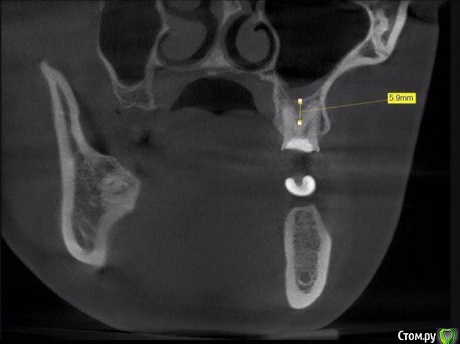

kamranchick Опубликовано 25 февраля, 2016 Поделиться Опубликовано 25 февраля, 2016 (изменено) Приветствую всехИмеется следующая картинаплан действия такойустановка имплантата на нижнюю челюсть в область верхнего зуба, удаление зуба и аугментации gen-os(Ostebiol) 0,5грамм сверху губка Ильгамовская( не владею техникой по Скляру) ну и перекрестные швыСразу не иду на одномоментную так как зуб резорциненный, и чуйка есть тут не торопиться)) ваши советы Изменено 25 февраля, 2016 пользователем kamranchick Ссылка на комментарий

red_butler Опубликовано 25 февраля, 2016 Поделиться Опубликовано 25 февраля, 2016 хочется, чтобы получилось так, чтобы через пару месяцев не идти на открытый синус...Предположу около семи мм высоты при отсроченном протоколе. 1 Ссылка на комментарий